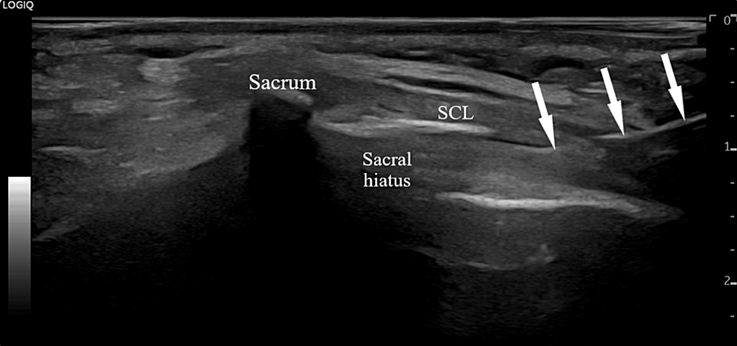

痛みの原因となっている神経の周りに、局所麻酔薬やステロイド薬を注射し、炎症と痛みを強力に抑えます。エコーで神経の位置を正確に確認しながら行うため、安全かつ効果的です。

図:エコー下での仙骨硬膜外ブロック(白矢印は注射針)

出典:Teixeira, A., & Barbosa, J. (2023). Paraplegia Following Ultrasound-Guided Caudal Epidural Block in Chronic Lumbosciatica: What Can Be Learned From This Complication?. Cureus, 15(11)